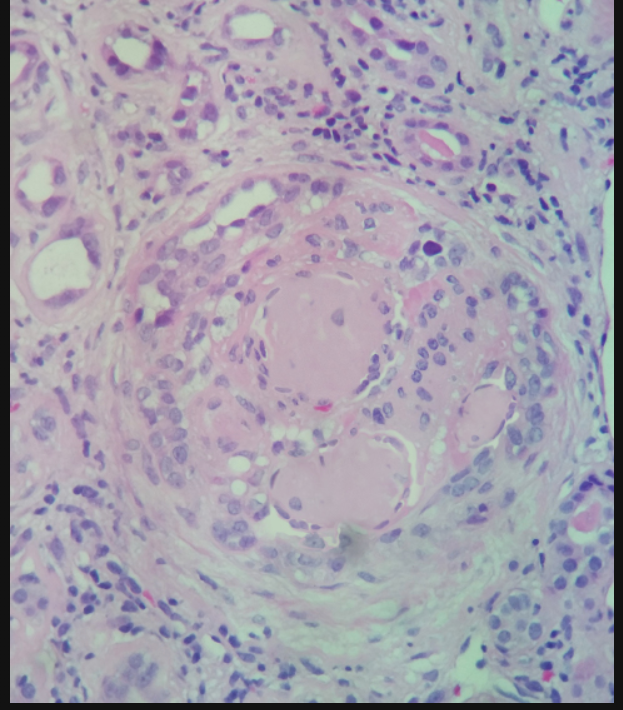

When the glomerular sclerosis is nodular, it is described as a Kimmelstiel-Wilson (KW) lesion and is pathognomonic for DN. KW lesions consist of dense hyaline deposits and commonly arise from the glomerular arterioles. As the disease progresses, increased mesangial matrix proteins can lead to global glomerulosclerosis.

Diabetic glomerulosclerosis